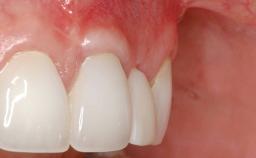

It is sometimes necessary to remove and replace compromised implants. This case is a clear example of the need for multiple steps to achieve an optimal therapeutic result for patients with non-salvageable implants. It illustrates how the lost soft and hard tissues were rebuilt in a sequence that improved the healing of the hard tissues and assured their long-term stability. The 35-year-old healthy patient presented with clinical attachment loss on the proximal and lingual surfaces of the natural dentition. Some gingival recession was present on natural teeth, particularly in the posterior sextants (S1, S3, S4, and S6).